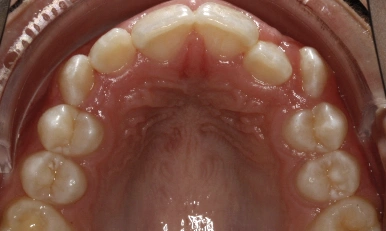

Patient Results